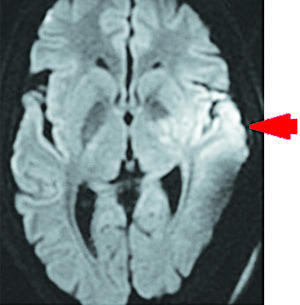

Результаты проведения МРТ головного мозга на 10-е сутки госпитализации (см. рис. 7 и 8). В области скорлупы и внутренней капсулы, в головке хвостатого ядра и паравентрикулярном белом веществе определяются сливные очаги гиперинтенсивного сигнала на Т2FLAIR и DWI, с умеренным ограничением диффузии на ADC, в бороздах мозжечка слева отмечается гиперинтенсивный сигнал на Т2FLAIR. Срединные структуры не смещены. Желудочки мозга не расширены. Субарахноидальные пространства конвекса не изменены. Признаков нарушения ликвородинамики не выявлено.

Базальные цистерны без особенностей. Селлярная область и основание черепа не изменены. Полость турецкого седла не расширена. Гипофиз обычных размеров и формы, контуры ровные, структура однородная. Дифференцировка на нейро- и аденогипофиз сохранена. Мосто-мозжечковые углы свободны, внутренние слуховые проходы не расширены, симметричны.

Краниовертебральный переход без особенностей. Миндалины мозжечка расположены обычно. На бесконтрастной ангиографии значимых деформаций, окклюзий артерий виллизиева круга не выявлено. В зону сканирования попадает стентированная часть левой ВСА с сохранным кровотоком.